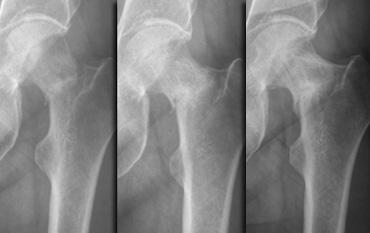

Hình bên trái: nữ bệnh nhân 15 tuổi, không có tiền sử chấn thương.

Đau vùng mu bàn chân phía ngoài khởi phát gần đây khi đi bộ.

X-quang tại thời điểm khám không ghi nhận bất thường.

Theo dõi sau 3 tuần cho thấy gãy hoàn toàn thân xương đoạn xa của xương bàn chân thứ 4 với phản ứng màng xương rõ ràng.

Hình bên trái: nữ bệnh nhân 39 tuổi với triệu chứng đau vùng mu bàn chân khởi phát trong kỳ nghỉ đạp xe.

X-quang tại thời điểm khám bình thường.

Tại các lần theo dõi sau 1 và 3 tháng, có thể quan sát thấy xu hướng lành xương rõ ràng, xác nhận sự hiện diện của gãy xương do stress.